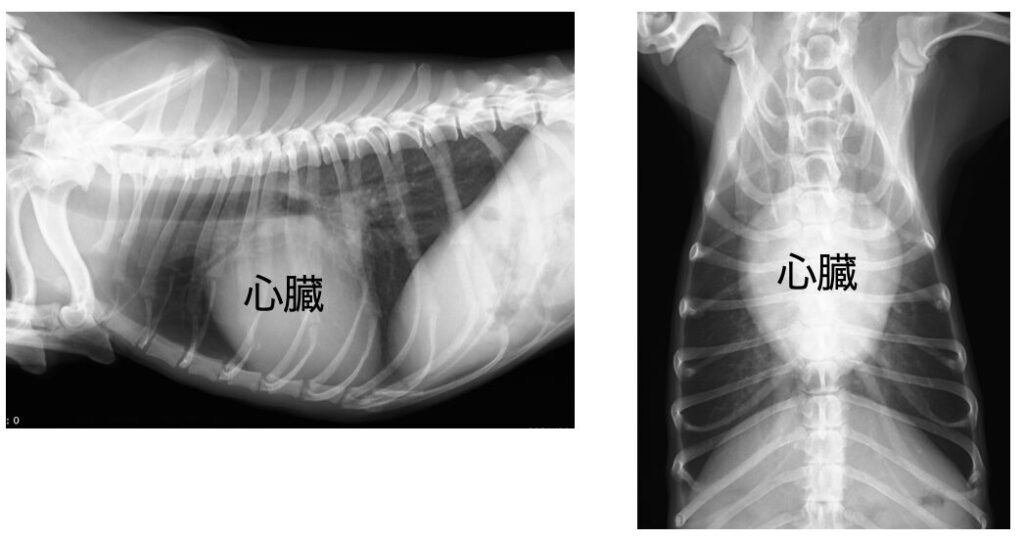

画像でわかる酸素不足・心肺機能の低下

生物は肺で血液中の二酸化炭素と待機中から取り込んだ酸素を交換することで、常に全身に新鮮な酸素を取り込んでいます。

ですが、上記画像のような肺では十分に酸素と二酸化炭素の交換が行われないため、健常者と同じ環境では酸素の摂取が不十分になってしまいます。

犬も人と同じように肺で酸素を吸収するため、肺が白く濁っている場合は同様に空気の交換がうまくできません。

この変化は画像で明確に確認できるため酸素不足の恐ろしさを視覚的に実感できます。